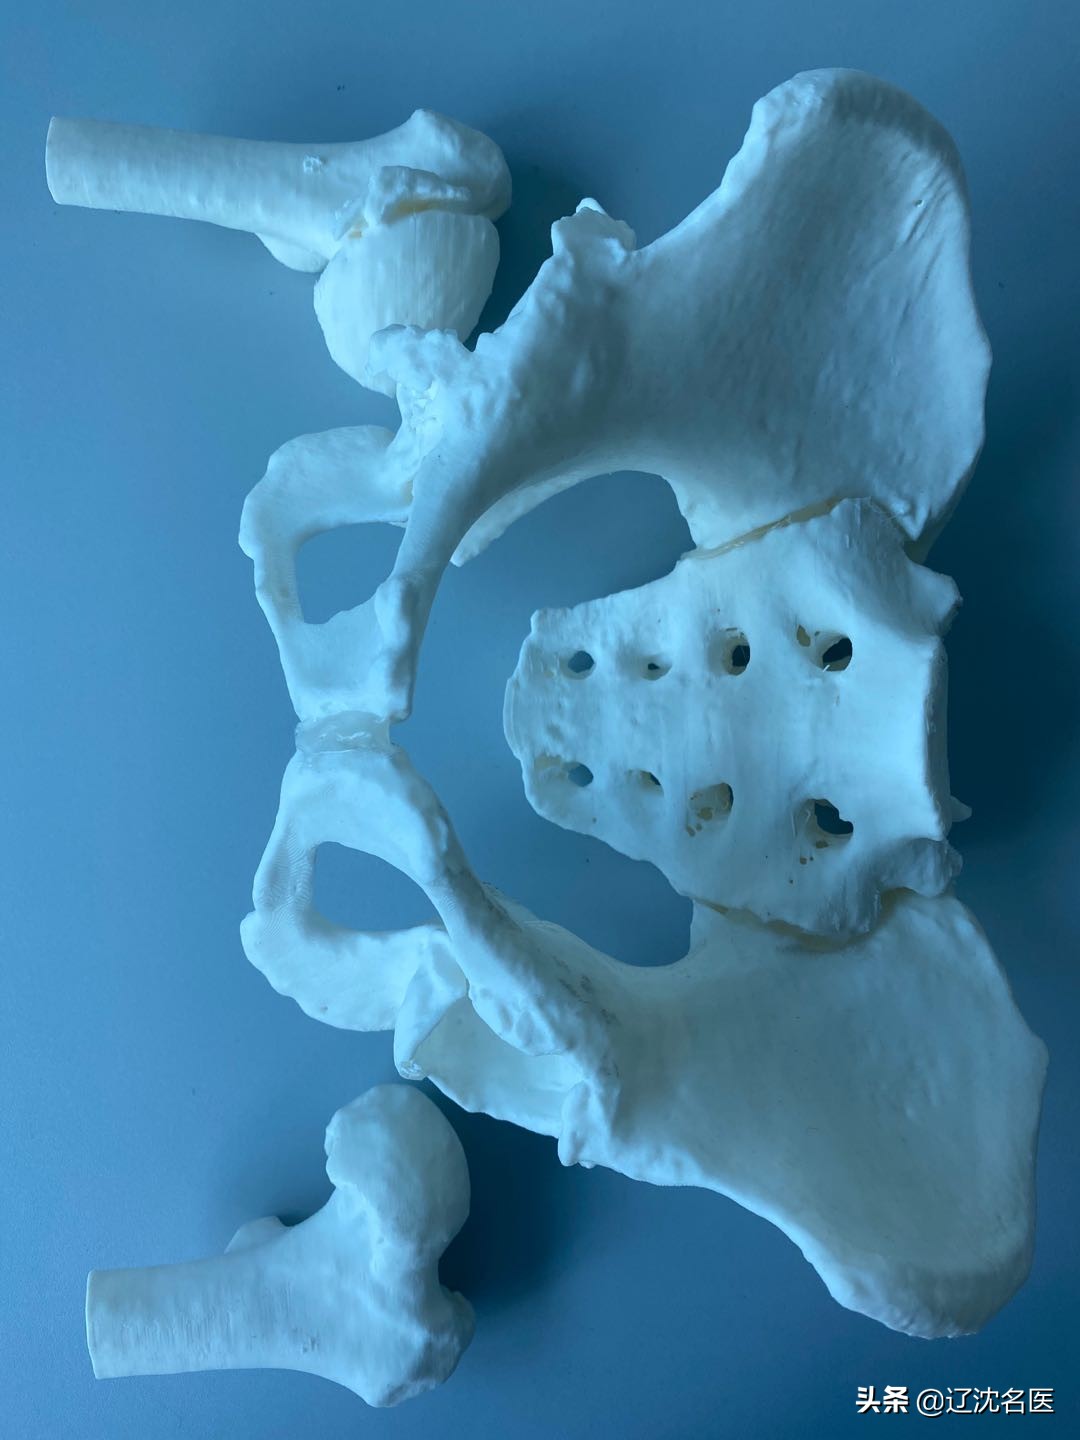

手术方法上,医生采用了3D打印技术,精准复原病变骨盆模型,成功为她置换了双侧关节;

同时,为确保手术安全顺利,骨科病房再度应用3D打印技术,与第三方合作,在放射线杨丽萍主任的配合下,成功打印出范女士的骨盆3D模型,结合模型科内医生又进一步的讨论,制定了详细的手术方案。

3D打印技术,指的是什么?在骨科治疗领域,它是数字骨科的标志性技术之一,可以协助骨科医生实现精准医疗,让骨科治疗更逼真,提高手术效率和术后疗效,缩短手术时间。